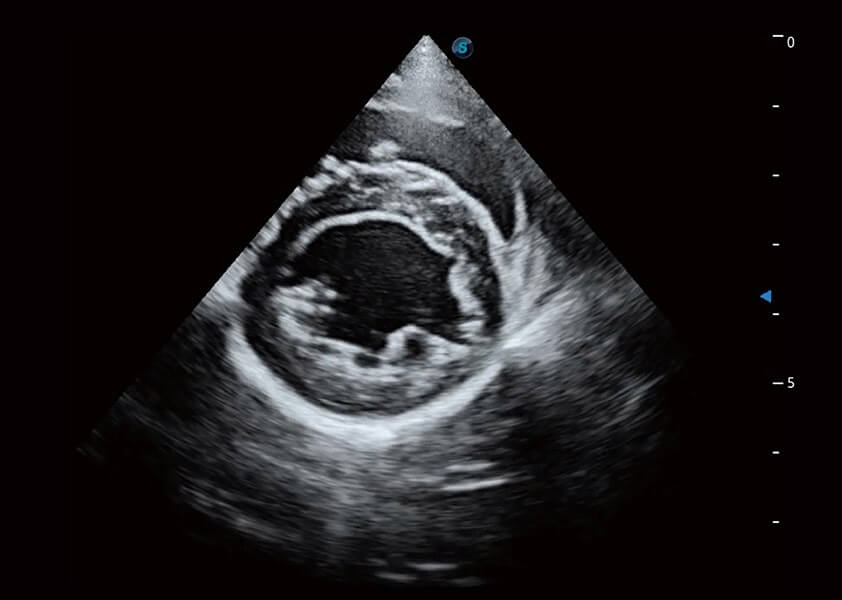

ProPet 60 作為一款高端臺式動物超聲設(shè)備,為動物醫(yī)生的日常診斷提供了一系列貼合動物臨床需求、解決臨床實際問題的高級成像功能。憑借全系列高清探頭,滿足醫(yī)生對腹部、心臟、生殖、淺表、肌骨等成像的所有需求,切實幫助您提升檢查效率,提高診斷信心。

動物是人類最親密的朋友和最值得信賴的伙伴。開立醫(yī)療也一直致力于探索動物專用的超聲影像解決方案。 全新推出的ProPet系列,是開立在動物超聲影像智能化、專業(yè)化、精準(zhǔn)化的一次跨越式革新。動物不能用言語來表述自己的不適,通過超聲影像,ProPet系列搭建了動物醫(yī)生與不同物種溝通的“橋梁”,為動物醫(yī)生注入了“治愈之力”。